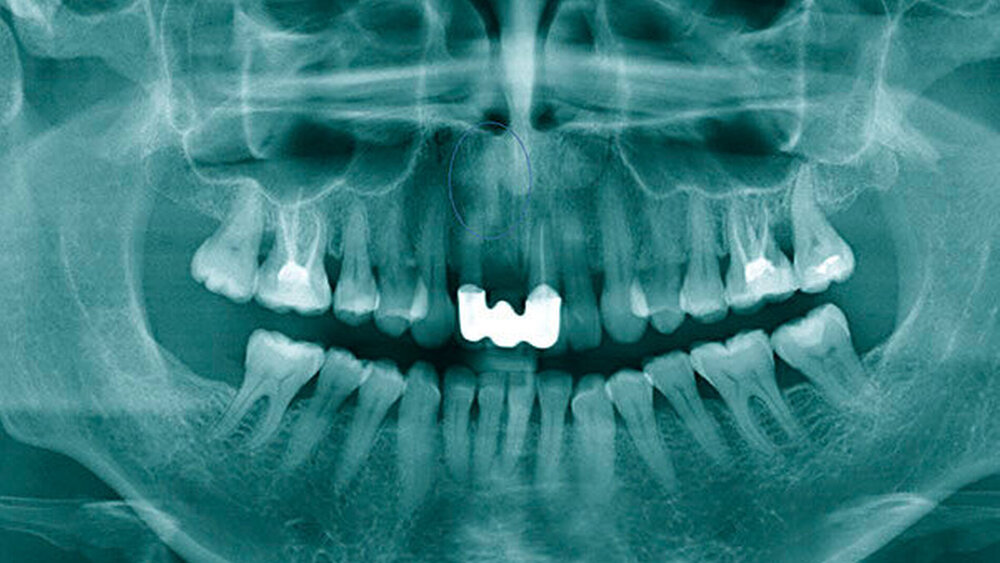

Eine 48-jährige Frau stellte sich in unserer Abteilung vor, nachdem ihr Zahnarzt im OPG einen Fremdkörper apikal der Alveole von Zahn 11 (Abbildung 1) diagnostiziert hatte. Das Röntgenbild wurde im Zuge einer angestrebten Implantatplanung in Regio 11 angefertigt. Bis dato war die Patientin mit einer Brücke von 12–21 in der Oberkieferfront versorgt, nachdem sie im Alter von neun Jahren Zahn 11 bei einem Sturz verloren hatte. Nach eigenen Angaben habe man damals versucht, den Zahn zu replantieren. Nach vorübergehendem Erfolg der Reinsertion des Zahns sei dieser nach einiger Zeit allerdings wieder verlustig gegangen. Es erfolgte die Versorgung mit einer provisorischen, später mit einer definitiven Brücke. Über den Vorgang der Replantation, die Verwendung eines Wurzelstifts oder den Verbleib des Stifts im Oberkiefer war der Patientin nichts bekannt. Im Zuge der Implantatplanung wurde ein DVT angefertigt, das den Verdacht eines Fremdkörpers, weit apikal der ursprünglichen Insertionslokalisation, bestätigte (Abbildungen 2 und 3).